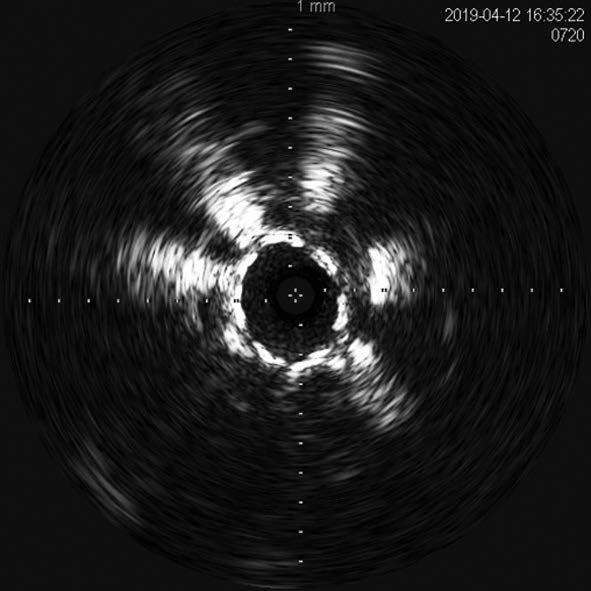

右大腿動脈穿刺、0.035 inchワイヤーを用いて、ガイディングシース 6 Fr 60 cmを左外腸骨動脈まで誘導し、造影を行った(図1.2)。体表面エコーガイドのもと、マイクロカテーテルと0.014 inch フロッピー300 cmワイヤーで、確実に浅大腿動脈入口部から血管真腔内を進めた。0.014 inch フロッピー300 cmワイヤーを抜去し、血管狭窄部貫通用カテーテルに交換し、閉塞部位を慎重に進め、貫通に成功した。血管狭窄部貫通用カテーテルにエクステンションワイヤーをつなげ、マイクロカテーテルを抜去、0.018 inchの径 2.0/長 20 mmバルーンで閉塞部位を拡張した。マイクロカテーテルを末梢まで進め、血管狭窄部貫通用カテーテルを抜去、0.014 inch 300 cm ワイヤーに交換、血管内超音波で病変部の観察を行った。ほぼ真腔を捉えていることが確認できたため、径 4.0/長 250 mmバルーンで閉塞全域を拡張した。一部石灰化病変により、拡張不良部位を認めたため(図3)、径 3.0/長 40 mm ノンコンプライアントバルーンで追加拡張を行った。再度、径 4.0/長 250 mmバルーンで閉塞全域を拡張した(図4)。血管内超音波で閉塞領域を観察し、ほぼ真腔を捉えていることが確認できた。ついで、径 5.0/長 250 mmバイアバーン® ステントグラフトを留置し、グラフト内をバルーンで後拡張した。血管内超音波でグラフト拡張および浅大腿動脈入口部を確認した(図5.6)。結果、左浅大腿動脈の良好な血流を得た(図7)。